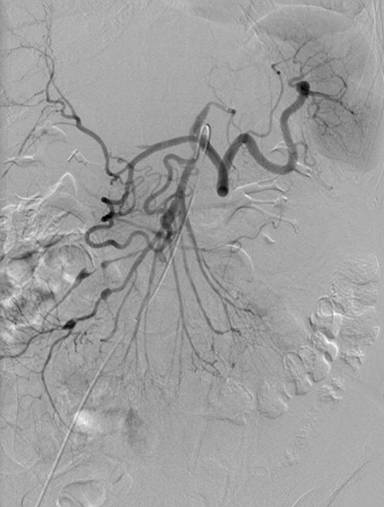

A 64-year-old Caucasian female was referred to our facility for further management of hemorrhagic pancreatitis. The patient had previously presented to an outside hospital with acute onset of severe sharp mid-abdominal pain, back pain, and nausea. She had no prior history of pancreatitis or alcohol use and had a prior cholecystectomy. Initial laboratory tests revealed a normal lipase, calcium, and triglyceride level. She had a history of hypertension, emphysema, depression, and spinal stenosis. She also had breast cancer 13 years prior, which had been treated by lumpectomy, chemotherapy, and radiation. Computed tomography (CT) scan displayed a heterogeneous fluid collection 14.3x11.2x10.0 cm and was interpreted as hemorrhagic pancreatitis involving the body and tail of the pancreas. Before admission to our hospital, she had required intensive care unit support including intravenous antibiotics and a transfusion of one unit packed red blood cells. She was started on total parenteral nutrition and took nothing by mouth. After seven days of support, she continued to have abdominal pain and was referred to our institution. Upon arrival to our facility, the patient was hemodynamically stable and afebrile. A repeat CT of the abdomen with intravenous contrast was performed at our facility 17 days after initial outside presentation (Figure 1), and it demonstrated a heterogeneous fluid collection 9.1x5.8 cm in the anterior pararenal space inferior to pancreatic tail, which likely represented a hematoma. There was also a 6 mm small pseudoaneurysm within the central portion of the fluid collection. There was no evidence of pancreatitis. An angiogram was subsequently performed and demonstrated dilatations and strictures with multiple pseudoaneurysms in the branches of the superior mesenteric artery, inferior mesenteric artery, ileal colic artery, and hepatic arteries, with one being adjacent to the pancreas (Figures 2 and 3). An attempt to embolize the pseudoaneurysm within the hematoma was unsuccessful due to tortuous mesenteric arteries. Other laboratory data obtained included C-reactive protein at 36 mg/L (reference range: 0-8.0 mg/L) and erythrocyte sedimentation rate of 72 mm/h (reference range: 0-29 mm/h). The workup for vasculitis included anti-nuclear antibodies, anti-citrullinated protein antibodies, rheumatoid factor, anti-double stranded DNA antibodies, and complement levels, all of which were within reference limits. Proteinase antibodies and myeloperoxidase antibodies were also negative. Her leukocyte count was not elevated and blood cultures were negative for growth. There was no history of congenital vascular disorders. She had no skin lesions and no renal or neurological abnormalities. A diagnosis of segmental arterial mediolysis was given based on exclusion and imaging. The patient was monitored in the hospital setting for 6 days after transfer and remained hemodynamically stable. Once abdominal pain resolved and the patient was tolerating a regular diet, she was discharged with close follow-up. A CT angiogram conducted four (Figure 4) and eleven months later (Figure 5) revealed resolution of mesenteric pseudoaneurysms and peripancreatic hematoma.

Figure 3. Superior mesenteric angiogram demonstrating vascular irregularity and pseudoaneurysm formation in the right colic, ileocolic and ileojejunal branches, as well as irregularity and pseudoaneurysm formation of multiple right hepatic arteries. |